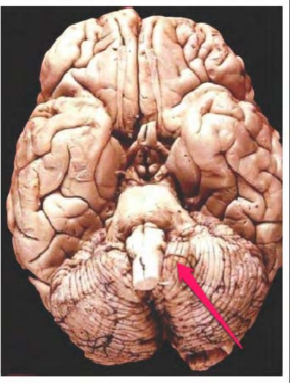

tonsilla cerebelli sin.

pyramis sin. medullae oblongatae

medulla oblongata

chiasma opticum

corpus mamillare dex.

a. basilaris

pons

crus cerebri Dex.